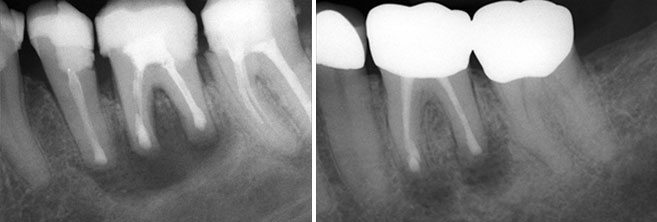

Dringen Kariesbakterien tief in den Zahn ein, können diese Entzündungen herbeiführen, die unbehandelt im schlimmsten Fall zum Zahnverlust führen. Bei einer Wurzelbehandlung werden Bakterien und restliches Nervengewebe aus dem Wurzelkanal entfernt. Dieser wird anschließend gereinigt und desinfiziert. Die Arbeit mit einem hochauflösenden OP-Mikroskop ermöglicht es uns, selbst feinste Wurzelkanäle genau zu betrachten und zu reinigen.Der entstandene Hohlraum wird mit geeignetem Füllmaterial aufgefüllt.Während und nach der Behandlung werden Röntgenaufnahmen gefertigt, um den Behandlungsverlauf und -erfolg zu kontrollieren und zu dokumentieren.